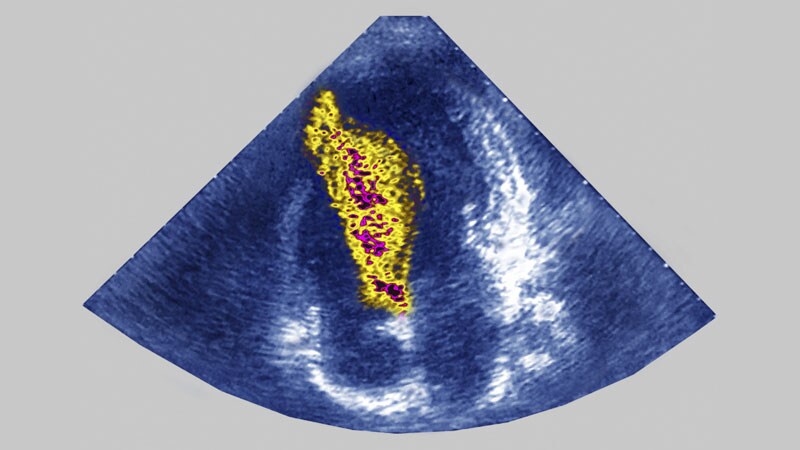

HFSA 2022Optimized HF Meds May Lessen MR Severity, Avoid Invasive TherapyPatients with heart failure and mitral regurgitation should get at least 6 months of optimized guideline-directed medical therapy before invasive mitral repair is considered, researchers say.